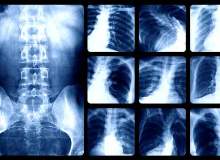

Reflü, mide asidinin ve mide sularının boğazdan mideye giden kanal boyunca tekrar yukarı çıkması anlamına gelir. Mide ekşimesine bu neden olur. Eğer haftada en az iki defa mide ekşimesi oluyorsa, buna mide ve yemek borusunun birlikte iltihabından kay